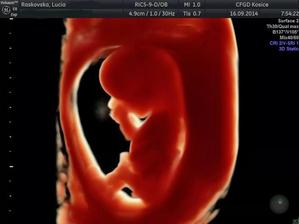

♥ 16.september prvotrimestrálny skriníng v 12tt (v Myslave) všetko v poriadku, odber krvi a máme prvé 3D fotky a na 80% potvrdené pohlavie 🙂